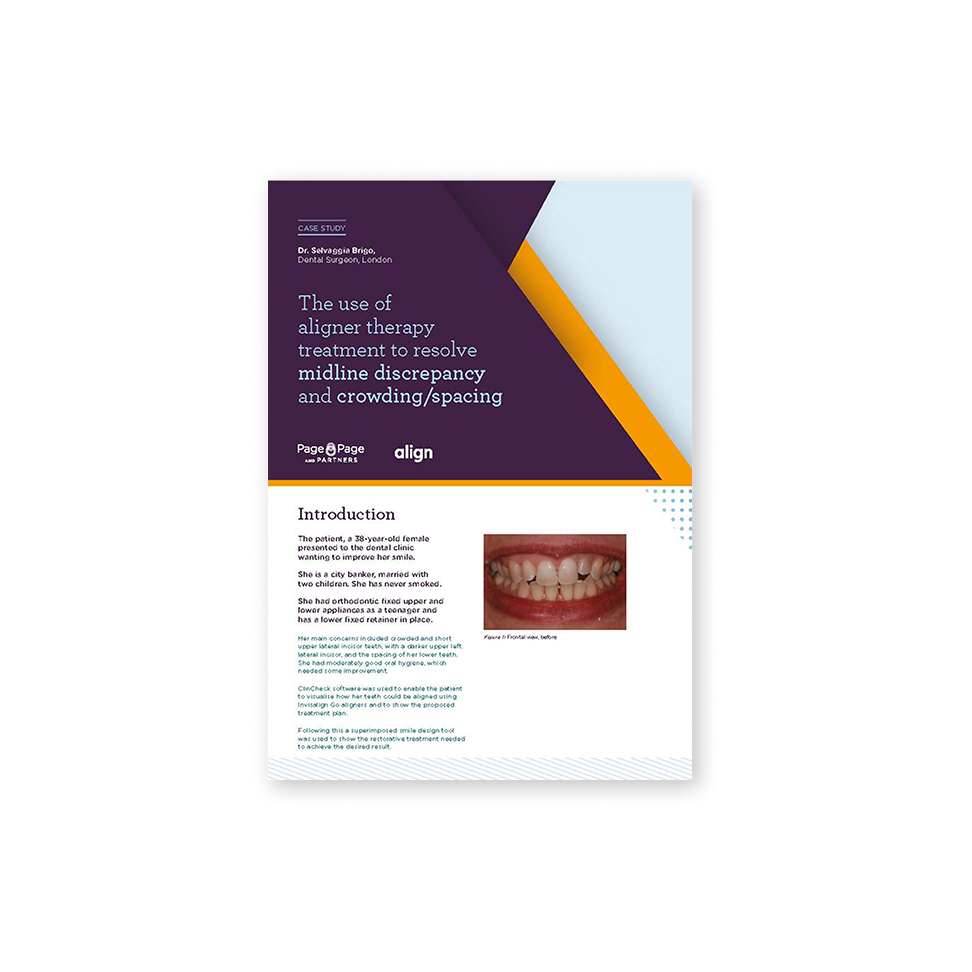

Midline Discrepancy & Tooth prominence

Midline discrepancy is the condition in which there is a misalignment of the midsagittal line of maxillary and mandibular arches respectively and/or relative to the facial midline.

Patient Information:

Age: n/a

Gender: Female

Invisalign Treatment Option: Invisalign Go

Total Treatment Time:

15 Months